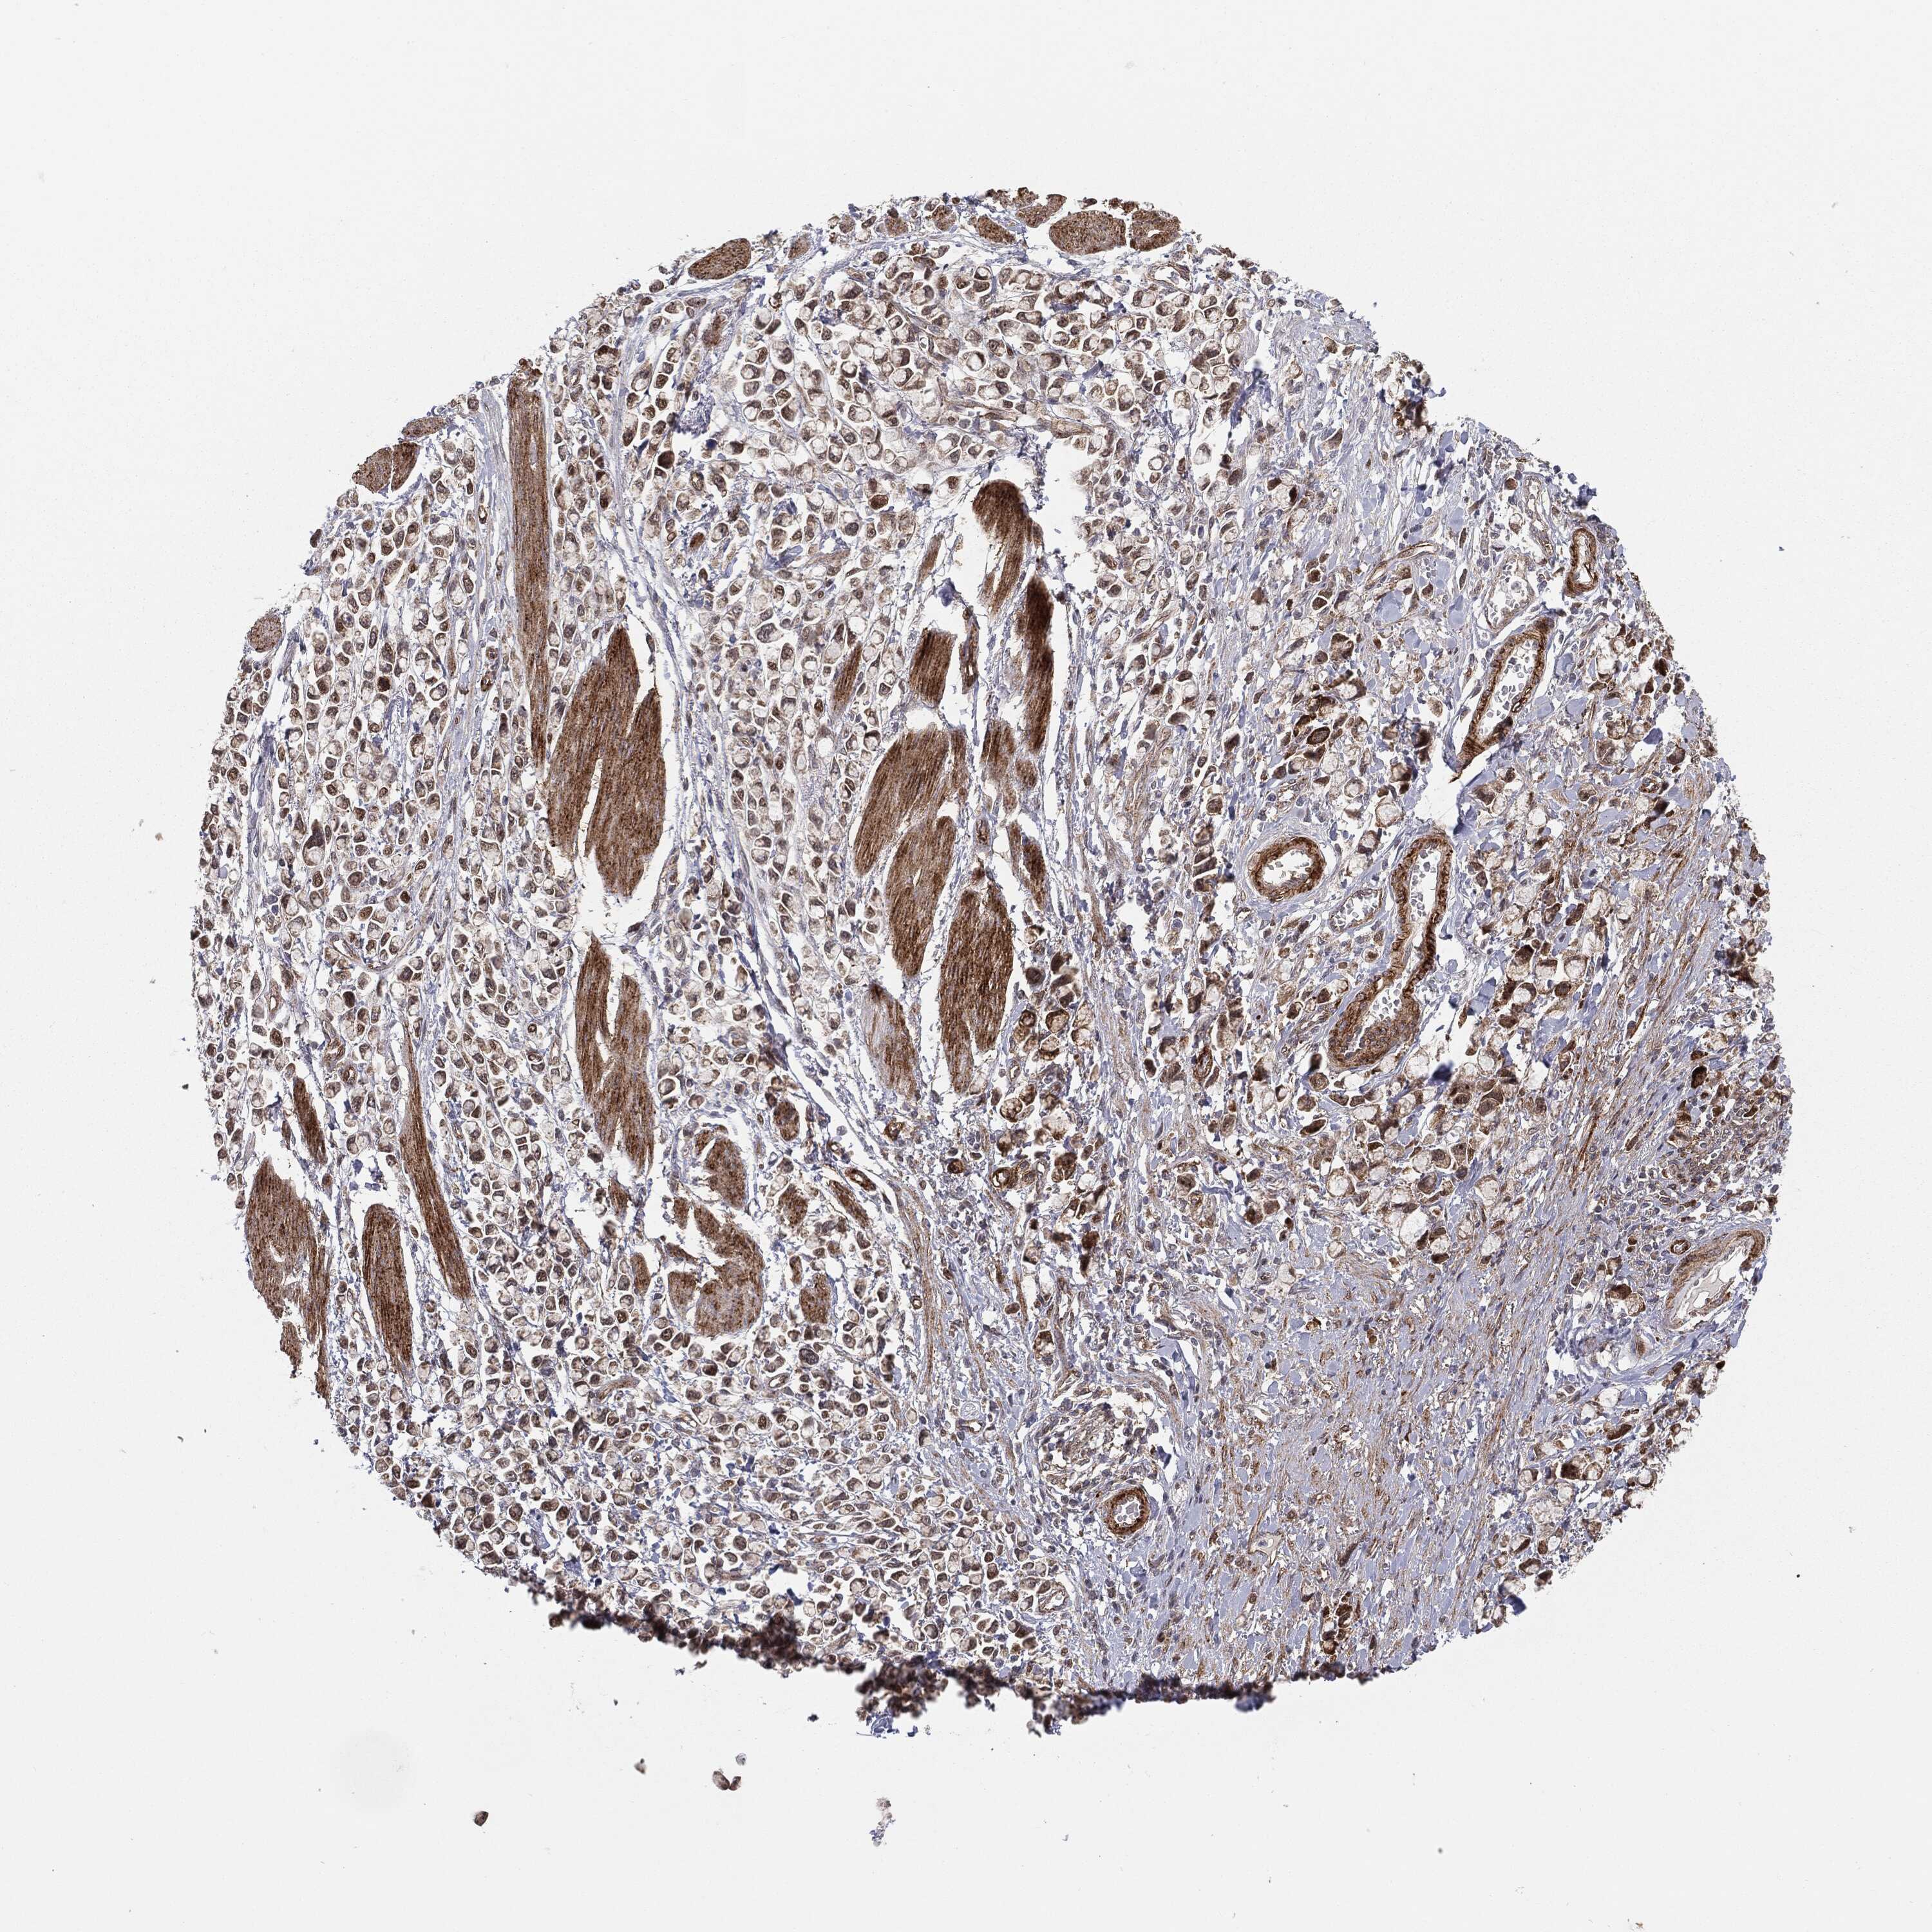

STOMACH CANCER - Protein expressioni

A mouse-over function shows sample information and annotation data. Click on an image to view it in a full screen mode. Samples can be filtered based on level of antibody staining by selecting one or several of the following categories: high, medium, low and not detected. The assay and annotation is described here.

Note that samples used for immunohistochemistry by the Human Protein Atlas do not correspond to samples in the TCGA dataset.

Antibody stainingi

Antibody staining in the annotated cell types in the current human tissue is reported as not detected, low, medium, or high, based on conventional immunohistochemistry profiling in selected tissues. This score is based on the combination of the staining intensity and fraction of stained cells.

Each image is clickable and will lead to virtual microscopy that enables deeper exploration of all samples and also displays staining intensity scores, fraction scores and subcellular localization as well as patient and tissue information for each sample.

Antibody HPA031335

Antibody CAB004076

Antibody CAB080153

Antibody CAB080157

Staining

High

Medium

Low

Not detected

Intensity

Strong

Moderate

Weak

Negative

Quantity

>75%

75%-25%

<25%

None

Location

Nuclear

Cytoplasmic/membranous

Cytoplasmic/membranous,nuclear

Adenocarcinoma, NOS

Adenocarcinoma, High grade